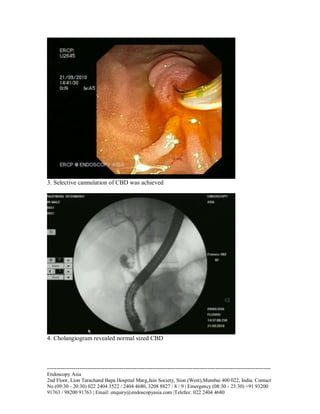

3. Selective cannulation of CBD was achieved

4. Cholangiogram revealed normal sized CBD